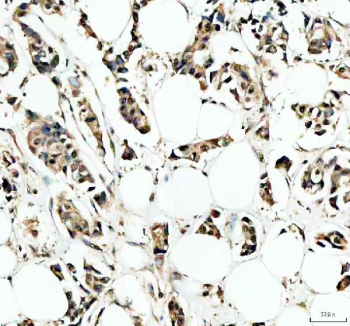

IHC staining of FFPE human breast cancer tissue with IRF9 antibody, HRP-secondary and DAB substrate. HIER: boil tissue sections in pH8 EDTA for 20 min and allow to cool before testing.